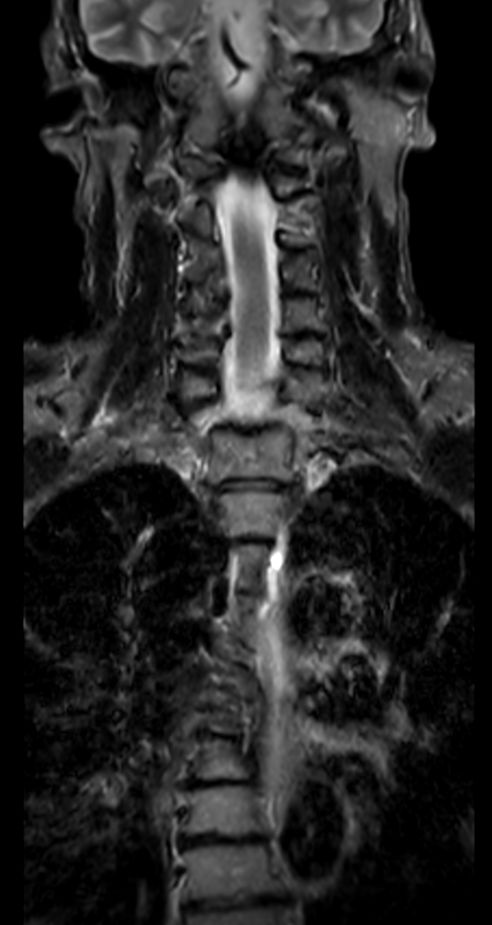

3D T2w TSE (SpineVIEW) - Coronal reformatCompressed SENSE

Coronal STIR TSECompressed SENSE